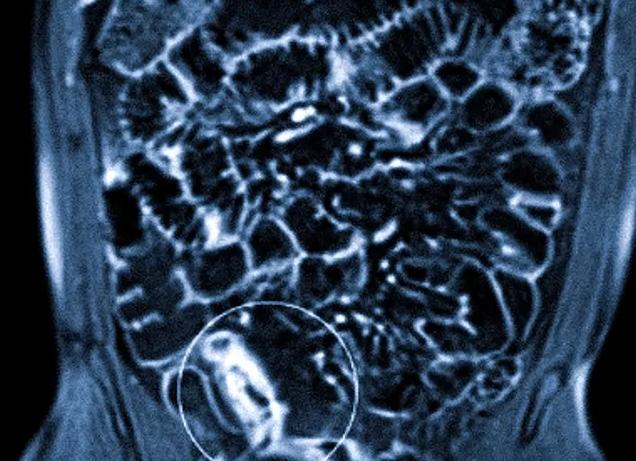

Гидро МРТ кишечника – это метод исследование его тонкого отдела, который относится к контрастной томографии. В его основе лежит двойное контрастирование – вещество принимается перорально и вводится внутривенно. В процессе выполнения диагностической манипуляции жидкость накапливается в полости кишечника и в его стенках.

В отличие от обычного сканирования, при гидро МРТ, когда кишечник наполнен раствором и присутствует в крови контраст, повышается точность исследования.

Гидро МРТ позволяет осмотреть все петли тощей и подвздошной кишки (около 8 метров)

Как правило, обследование занимает около 1 часа. Результаты записывают на диск или любой другой цифровой носитель. Поскольку петли кишечника накладываются друг на друга, то на снимках они представлены с различной четкостью.

Довольно часто МРТ тонкого кишечника проводится при помощи особой техники контрастирования. В результате получается особое гидро-МРТ исследование. Пациенту дается примерно 1500 мл специального двухфазного раствора с контрастными характеристиками. Принятый состав особым образом растягивает просветы кишечника. При это расправляются все сложные участки и изгибы, что значительно улучшает обзор кишечника по всей длине обследуемого участка. Если подозревается у пациента наличие кровотечения, больному вводится особый внутривенный контраст.

Отличие гидротомографии

Гидро МРТ кишечника проводится по специальной технологии применения двойного контраста. Пациент выпивает специальный раствор, что позволяет расправить складки кишечника, делает лучше обзор. Это даёт возможность рассмотреть в просвете все неровности, новообразования. Второе контрастное вещество вводится пациенту в вену. Это помогает просмотреть стенки кишки.

Во время гидро МРТ осматривается тонкий кишечник. Это полый орган, в некоторых случаях его осмотр может быть затруднён. Например, новообразования можно принять за складки. Современные методы диагностики снижают риск таких ошибок.

На сегодняшний день Гидро-магнитно-резонансная томография– это один из самых информативных и эффективных методов медицинского обследования всасывающего органа системы пищеварения. Различные отделы тонкой и толстой кишки детальным образом будут изучены. Любые формы патологических процессов и прочих недугов не останутся без внимания со стороны квалифицированных специалистов. Для получения точной и достоверной информации кишечник необходимо заполнить специализированной жидкостью. Именно по этой причине процедура носит название «Гидро-МРТ».

Гидро-МРТ – это наиболее информативная и эффективная методика диагностирования внутренних органов человека. Перед проведением процедуры кишечник наполняется водой, что существенно влияет на расправление стенок. Таким образом, открываются все опухоли и различные патологии (болезнь Крона, эндометриоз, колит язвенного типа, полипоз и пр.) Проведенные анализы и заключения дают реальную возможность специалистам установить соответствующее лечение. Пациент получает шансы на быстрое выздоровление.